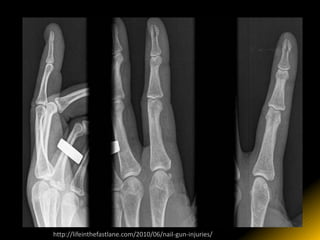

http://lifeinthefastlane.com/2010/06/nail-gun-injuries/